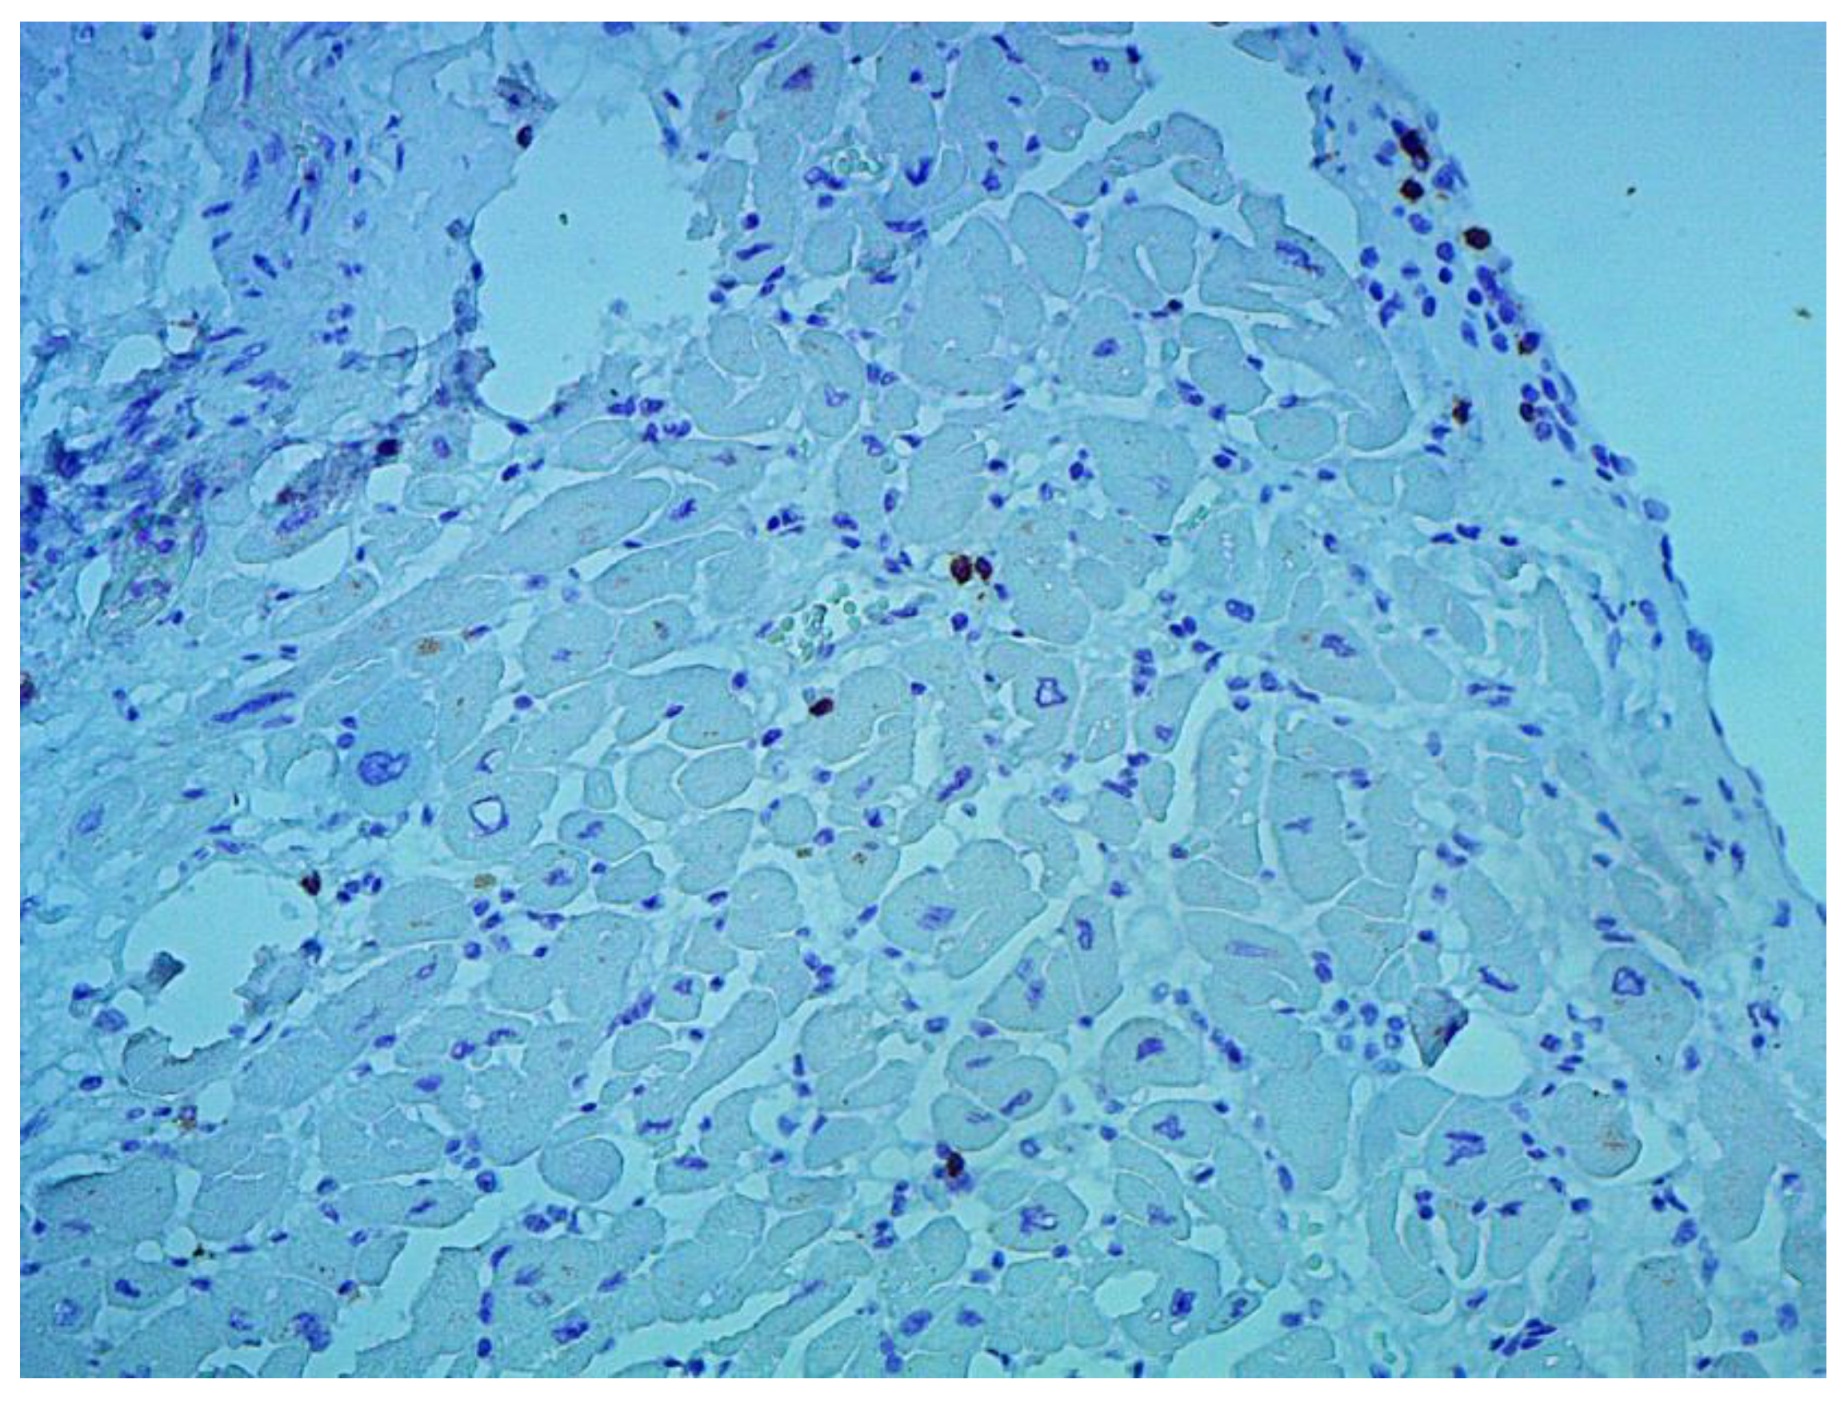

According to the Dallas criteria, the presence of histological myocarditis was revealed in 23 patients (34.3%) (Figure 6). Moreover, the virus expression was detected in 18 of these patients (78.3%), according to the results of immunohistochemical analysis. One patient (5.6%) was found to express three viruses: enterovirus, human herpes simplex virus type 1, and Epstein-Barr virus; six patients (33.3%) had the presence of two viruses: one patient had a combination of parvovirus and herpes simplex virus type 2; three patients had a combination of enterovirus and herpes simplex virus type 1; and two patients had a combination of Epstein-Barr virus and human herpes simplex virus type 2. The presence of one viral antigen was detected in 11 cases (61.1%), including five patients (27.8%) with Epstein-Barr virus, three patients (16.7%) with enterovirus (Figure 7), two patients (11.1%) with human herpes simplex virus, and one patient (5.6%) with parvovirus. Another five patients (21.7%) did not have viral infection.

Figure 7. Expression of the enterovirus antigen VP1 in the myocardium. Immunohistochemical study, monoclonal mouse antibodies, ×400.

Jcm 12 01254 g007